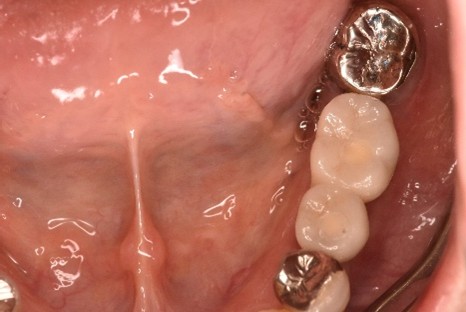

After

女性Mさん 40代(インプラント)